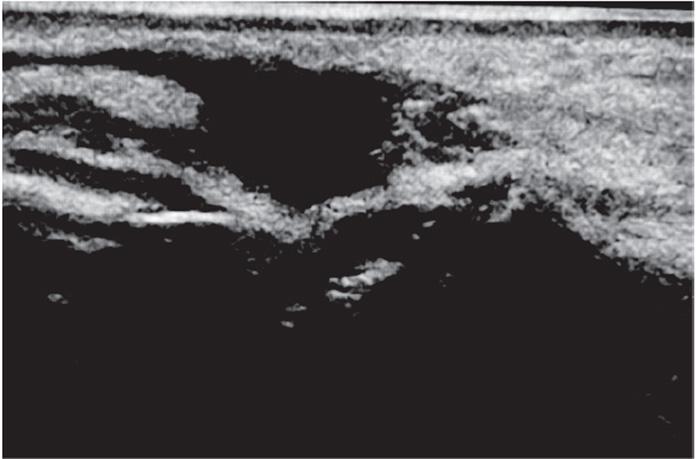

Typical ultrasound appearance of unwanted or residual HA filler is anechoic to hypoechoic, suggesting that the filler is reasonably well hydrated. One protocol consists of targeted treatment using microinjections of 15 IU, not exceeding 150 IU in total, administered in a radial pattern within unwanted (anechoic or hypoechoic) hydrated filler, dependent on volume of residual HA filler. Large quantities of HA filler (greater than 3 mL) could require repeat injections at one- or two-week intervals. Use of high-dose dose hyaluronidase flooding protocols (greater than 150 IU in a single session) is discouraged because of potential leakage into surrounding body tissues, risking an extended area of potential tissue breakdown. The effects of treatment are generally immediate, and a follow-up targeted ultrasound of the area shows no residual Ha filler (Figure 4) [98].